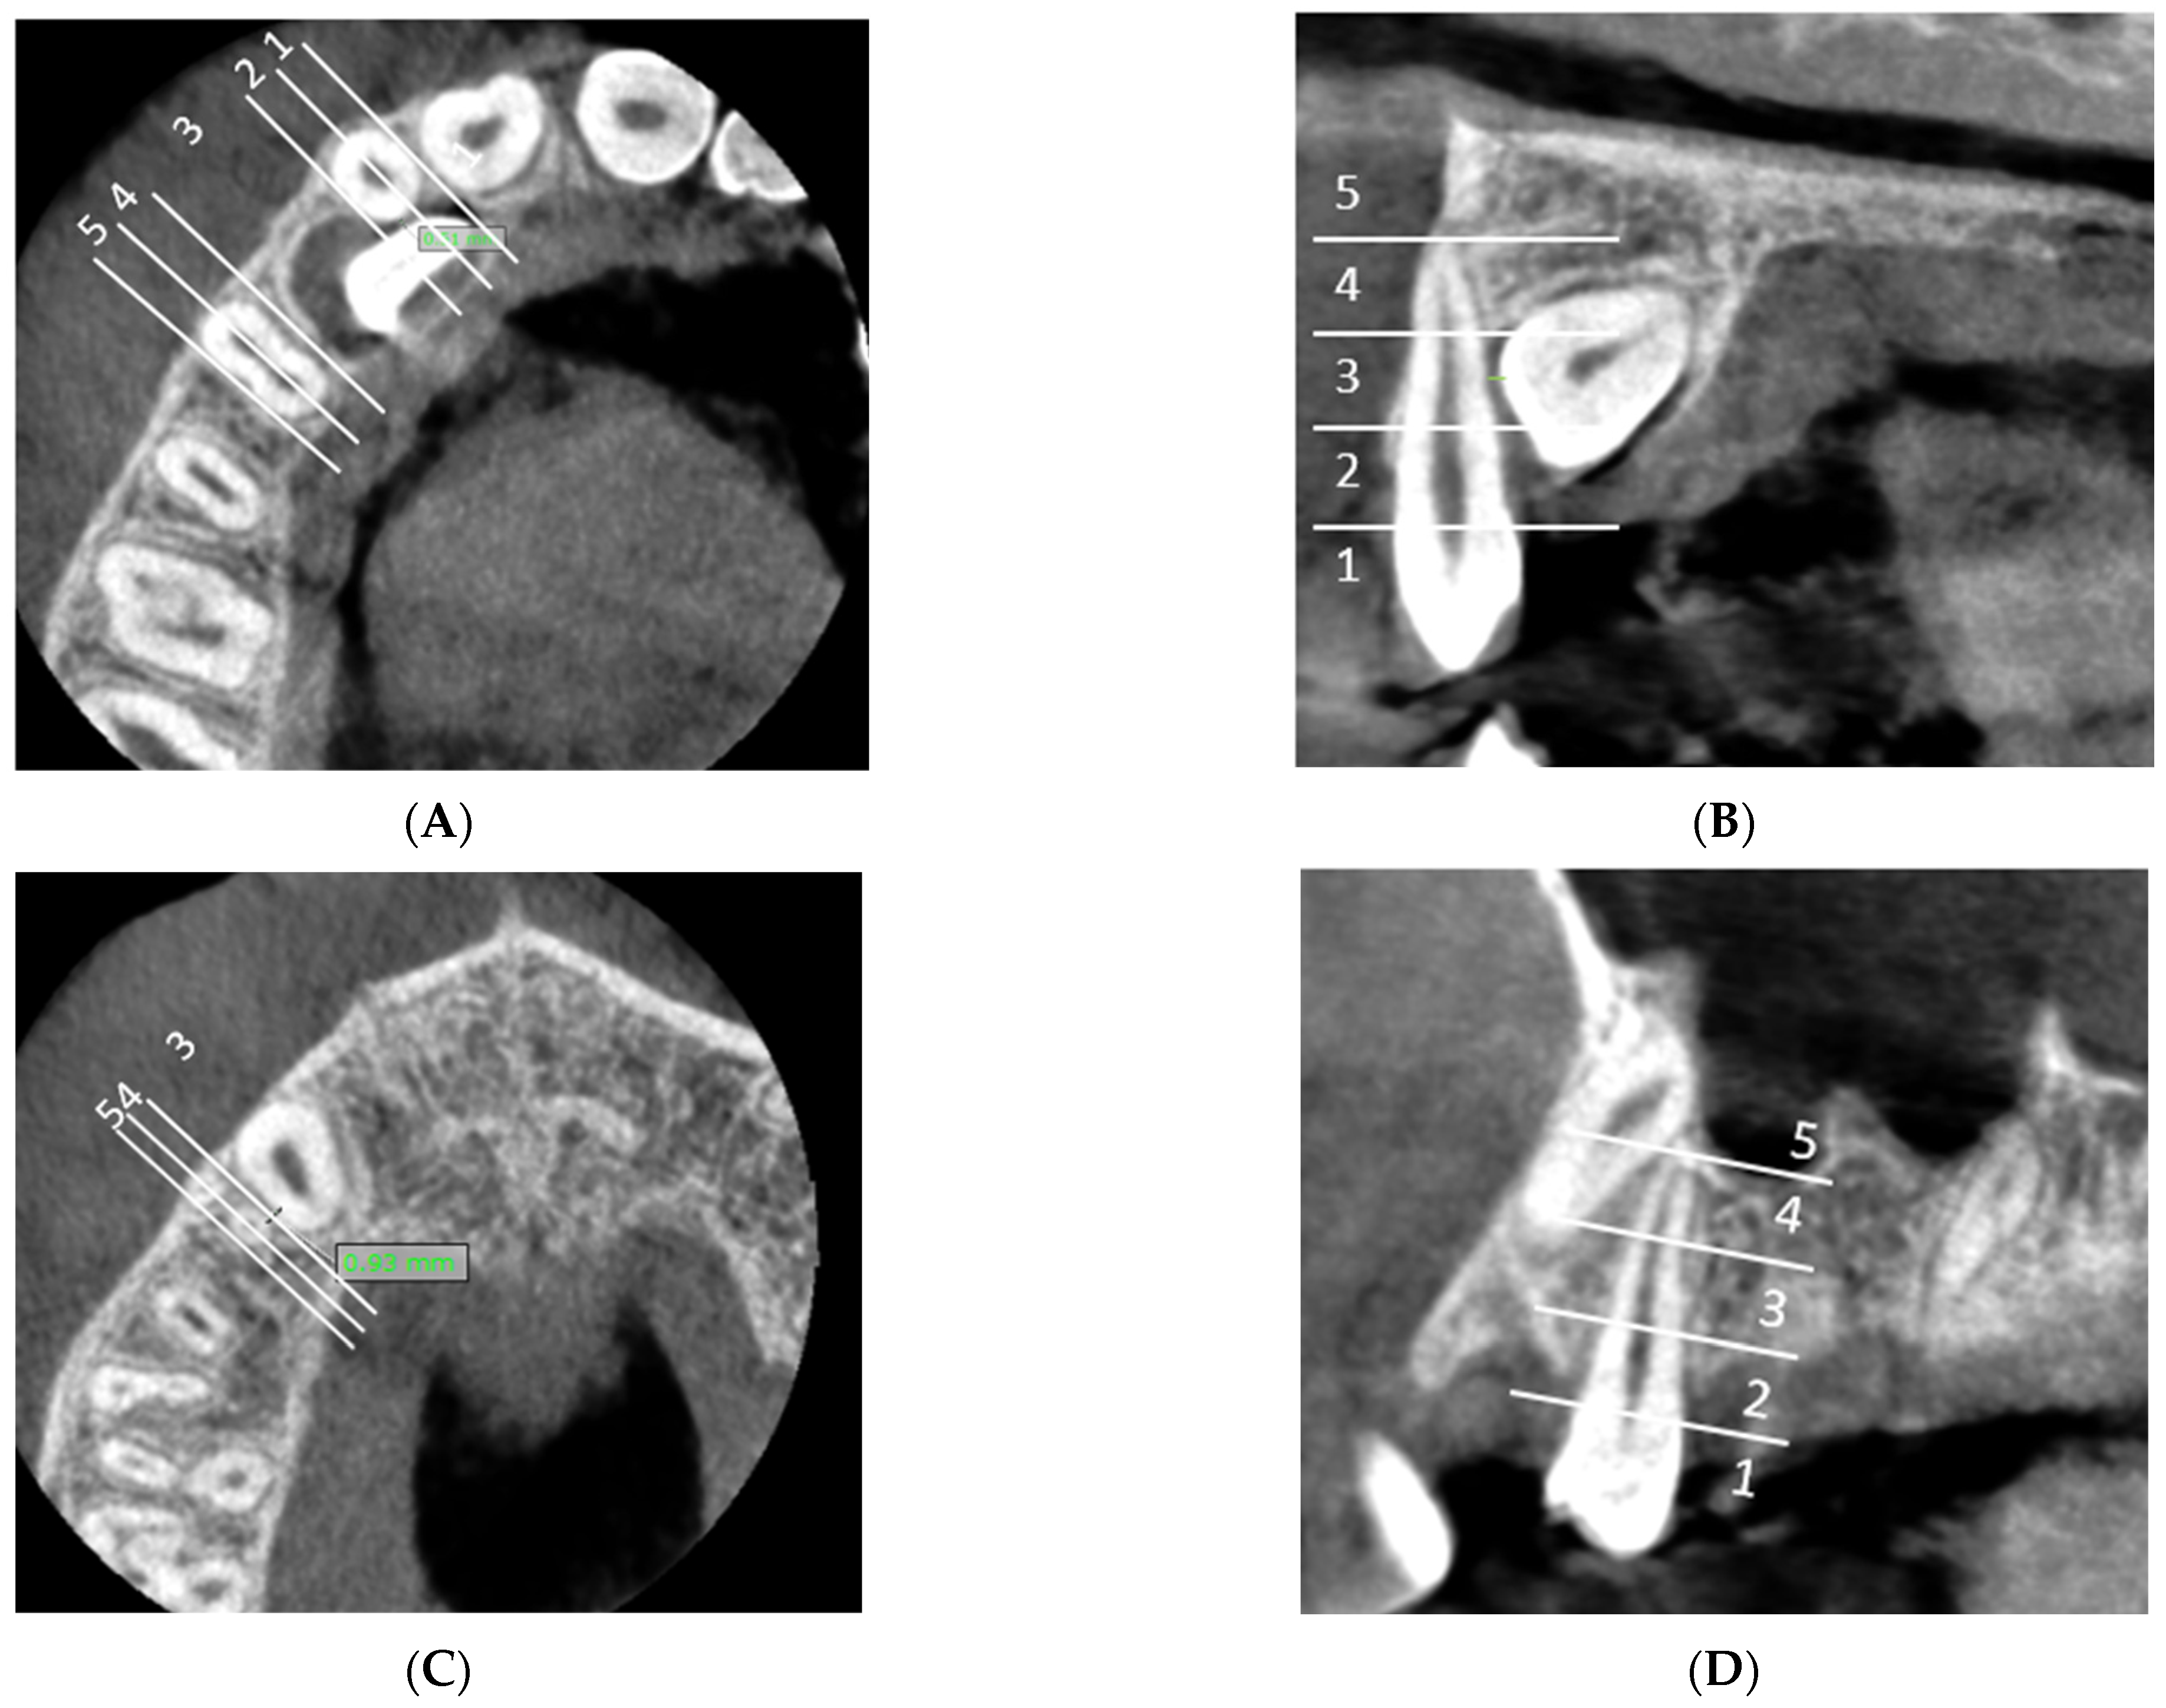

F: Measurement of the maximal follicle size of the impacted maxillary canine (Figure 4A).

Figure 4. (A) Measurement of the maximal follicle size of the impacted maxillary canine. (B) Measurement of the shortest distance between the impacted canine/dental follicle and the external cortical bone margin. The minimal distance between the dental follicle and the external cortical bone margin is 0 mm and the minimal distance between the impacted canine and the external cortical bone margin is 0.36 mm.

Dentistry 13 00497 g004

G: Measurement of the shortest distance between the impacted canine/dental follicle and the external cortical bone margin. (Figure 4B).